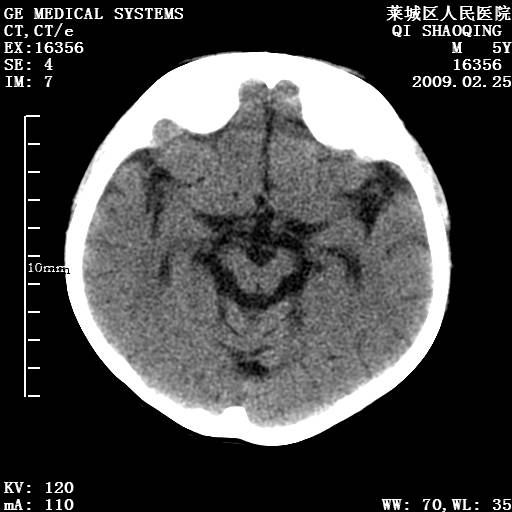

以下是引用wangzhengyuan在2009-2-28 10:22:00的发言:[br]甲状旁腺功能减退引起的脑改变.

以下是引用zsl6918在2009-2-28 10:17:00的发言:[br]首先考虑甲状旁腺功能低下所致,可结合实验室检查明确.另外需除外先天性宫内感染所致.

以下是引用余辉在2009-3-1 9:35:00的发言:[br]患者明显的肢体及智力改变,不支持fahr病,多考虑甲旁低,有可能伴有甲低(呆小症).进一步检查。